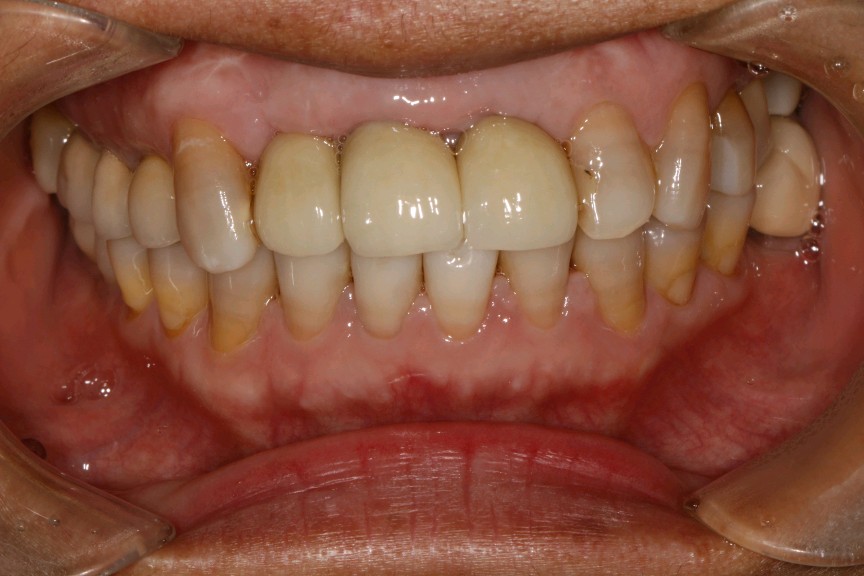

向患者交代病情、治疗计划、费用、预后等,患者知情并同意治疗。,抽静脉血20ml,12植入欧美 hiossen 种植体3.5*11.5mm,11.21植入欧美 hiossen 种植体4.0*11.5mm上覆盖螺丝,颊侧骨缺损区植入人工骨粉 傲骨0.5g及 CGF ,并盖百傲膜及 CGF 膜,严密缝和。二期三期如期进行与近日佩戴牙齿。

术后